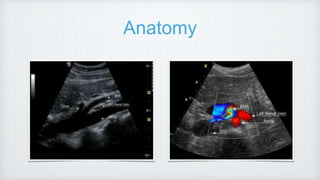

Anatomy

Right RA is retrocaval in location.

The left renal vein lies between the superior mesenteric artery and the aorta.

Circumaortic left renal vein

Renal arteries arise from proximal aorta just below origin of SMA.

• #3 3. One of the most common anatomic variants of the renal venous system is a circumaortic left renal vein, in which one of the limbs of the left renal vein courses anterior to the aorta and another one runs posterior to it. 4. RK is relatively inferior in its position, which explains a downward course of the rt RA, lt RA,, arises below the right renal artery from the aorta and is more horizontally.

• #4  ultrasound image is a sagittal view of the abdominal aorta. The left renal vein can be seen in its short axis between the SMA and aorta. The bottom right ultrasound image is a transverse color Doppler view showing the anatomical relationship between the SMA, celiac trunk, aorta, IVC and left renal vein